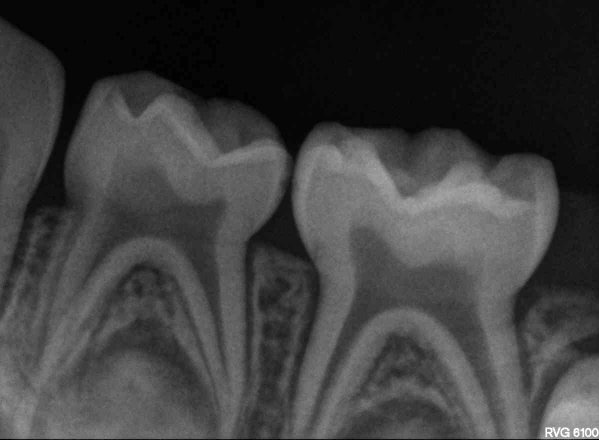

Сложно сказать, к моему большому сожалению, многие врачи забыли о своей заповеди и перешли на абсолютно коммерческую форму лечения. Не надо никому верить, сделайте снимок ОПТГ и выложите сюда.